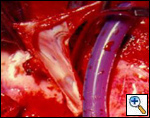

Tangential resection and venous plasty: in cases in which less than 30% of the SVC circumference is involved, a partial resection of the vessel can be performed. For minimal invasion, a tangential resection of the defect closed with a running suture or a vascular stapler is usually easy and leaves a patent vessel (Figure 6). Larger defects, especially if they are longitudinally extensive, require reconstruction; this can be obtained by the interposition of a patch of autologous or bovine pericardium (Figure 7). Autologous pericardium may be fixed in diluted glutaraldehyde (two drops of 20% glutaraldehyde in 50 cc of saline) for one minute to let it stiffen and facilitate manipulation during suturing.

SVC replacement: replacement of the whole body of the SVC is the most frequent type of reconstruction (Figure 8). In patients with lung cancer, it is usually associated with right upper lobectomy or pneumonectomy; however, SVC reconstruction may be required during carinal pneumonectomy, sleeve lobectomy (Figure 9), and reconstructive procedures of the pulmonary artery[5]; the latter two should always be attempted if they help to avoid pneumonectomy. SVC replacement requires a tumor–free confluence of both brachiocephalic veins. The reconstruction is usually performed using a straight non-ringed PTFE graft (18 – 20 mm). An autologous or bovine pericardial tube could also be used (Figure 10). After proximal and distal clamping, the SVC is excised. The proximal anastomosis is performed first, using a 5-0 polypropylene suture, starting from the posterior aspect of the prosthesis or the tube of pericardium. The distal anastomosis is subsequently performed with the same technique. Before tying the distal suture line, the proximal clamp is gently released and deaeration is performed; afterwards, the distal clamp is released and knots are tied. After complete filling of the graft by blood, there should be no tension of the suture lines or torsion or kinking.